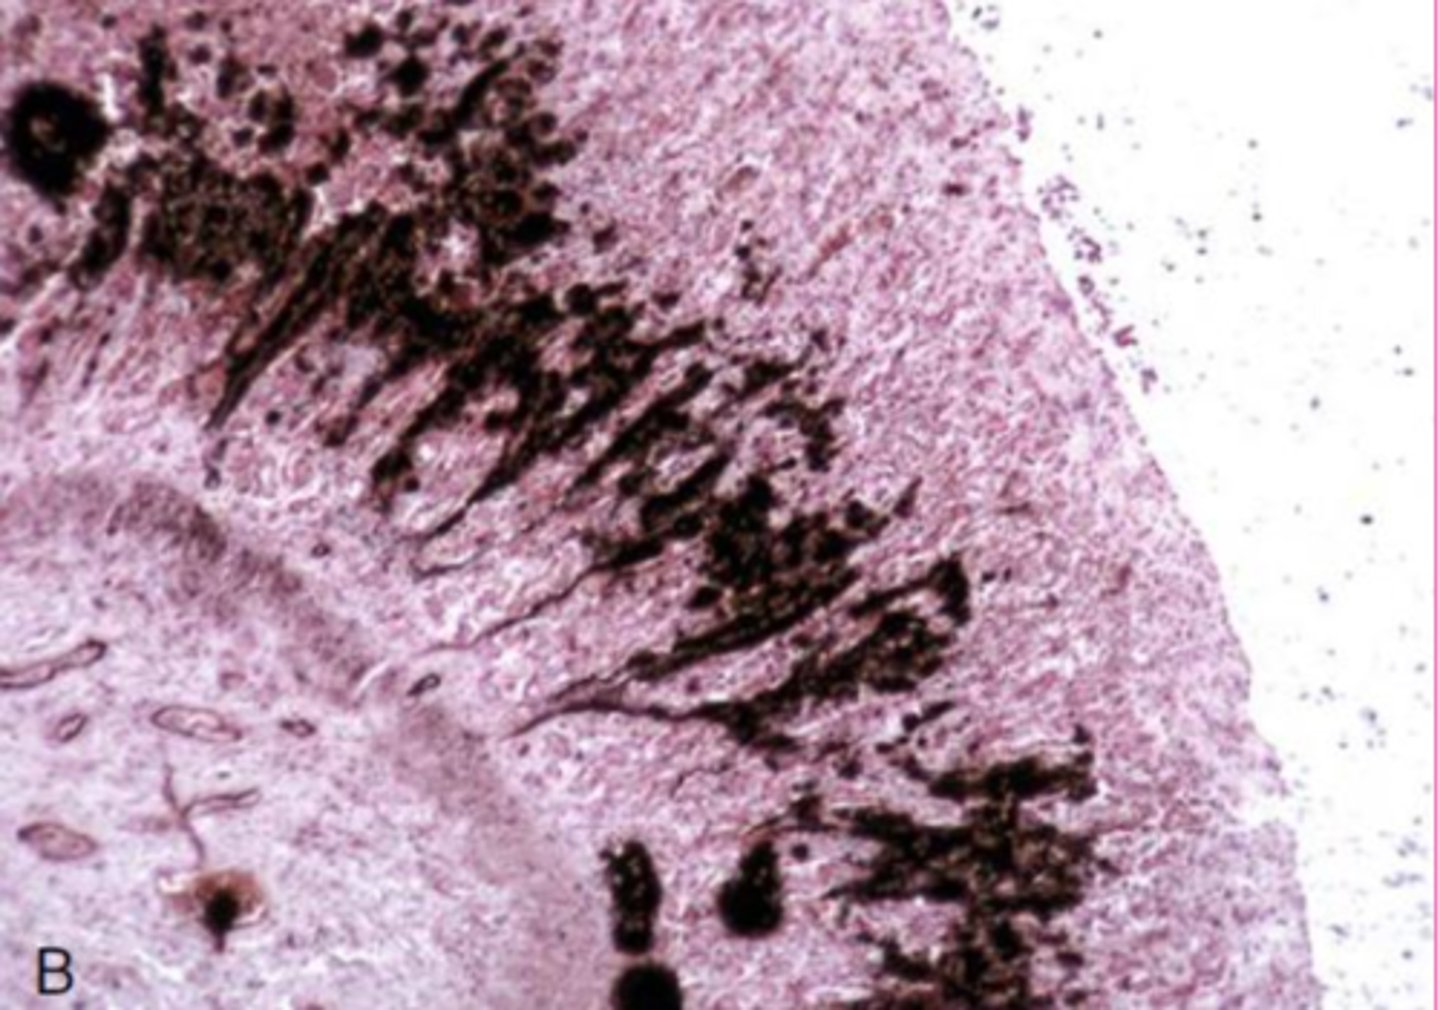

hyaline casts

What extracellular inclusion?

<p>What extracellular inclusion?</p>

8